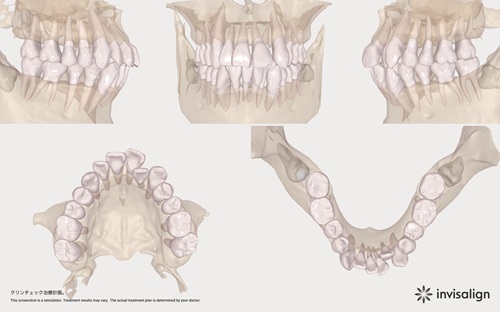

矯正前シミュレーション(クリンチェック)

インビザラインを使用した矯正歯科治療における特徴のひとつと言えるものが、「クリンチェック」です。インビザラインにおいて、最重要なものでもあります。

クリンチェックとは、コンピューター上で矯正時の歯の動きをシミュレーションして治療計画を立てるためのシステムで、安全かつ確実な矯正歯科治療を行うためには欠かせません。 当院では、より患者さまのご要望に合わせた治療や安全性の高い治療を行うためにクリンチェックを重視し、場合によっては複数のプランを立てた上で選択できるようにしています。

歯の動きのシミュレーション

歯がどのように動くのか、治療のゴールをご自身の目で見ていただくと、とても分かりやすくご好評をいただいております。※下部に動画があります。

歯の動きのシミュレーションを動画にしました

マウスピース矯正計画(クリンチェック)を動画にしたもの

上の数字がマウスピースの数です。